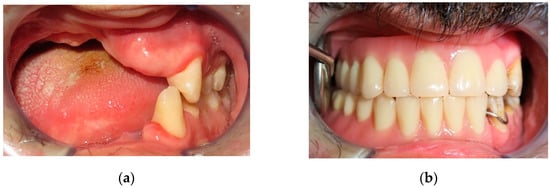

Figure 1.

A 41-year-old female patient wounded by a low-velocity injury weapon. (a) Before prosthetic treatment; (b) after prosthetic treatment.

Intraoral view: (a) temporary resin removable prosthesis; (b) after a fornix depth surgery; (c) implant surgery; (d) final implant-retained prosthesis.